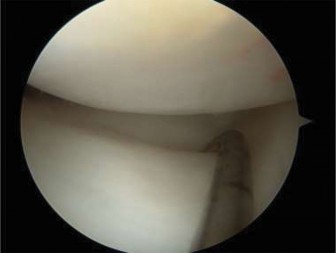

The correct answer is (B). If the patient were asymptomatic, then the discoid meniscus could simply be observed with a return to unrestricted sporting activity. For a younger patient who is intermittently symptomatic and/or elects to not undergo operative intervention, lateral compartment unloader bracing may be appropriate until the patient and/or family agree to intervention. Long-leg casting is not appropriate and will do nothing more than cause stiffness, loss of strength, and range of motion. As the patient is symptomatic, has mechanical symptoms, and has potential tearing seen on MRI, arthroscopic intervention is indicated to examine the meniscus and intervene. The patient is taken to surgery, and intraoperative images ( Figs. 10–31 and 10–32 **) are shown. The next step in management is:**

Figure 10–31

Figure 10–32

The correct answer is (C). The arthroscopic images demonstrate a complete discoid meniscus which is covering the entire lateral tibial plateau. As the patient is symptomatic from the meniscus, saucerization is the first step in management. The meniscus is trimmed back using a combination of shavers and biters to a stable peripheral rim, which replicates the width of the native meniscus. Complete meniscectomy would not be indicated in a patient of this age due to the high risk of early onset degenerative arthritis. In fact, even prior to intervention, many discoid menisci have been associated with the development of lateral hemijoint osteochondral lesions. Although chondroplasty may be necessary, the meniscus is the underlying problem causing chondral wear and must be dealt with first. After saucerization is performed, the meniscus is probed and the following arthroscopic image is seen (Fig. 10–33). The next step in management is: